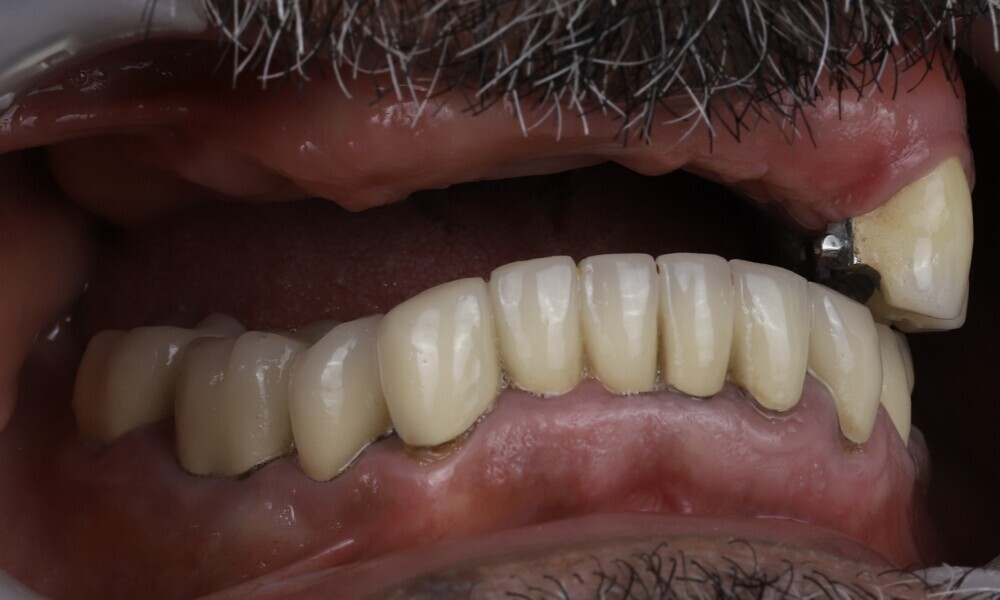

Extra-oral examination showed no significant abnormalities. The patient presented with a medium smile line (Figs. 1–3). The intra-oral examination revealed a fixed bridge spanning teeth #23–26 to which the removable metal partial denture attached (Fig. 4). Teeth #22–17 had been extracted a long time before, and the ridge in this region had healed. No plaque or inflammation was observed. The teeth exhibited mild to moderate attachment loss, but no endodontic or periodontic lesions or root fractures were observed (Figs. 5–8). Analysis of the panoramic radiograph indicated sufficient vertical and horizontal bone availability and adequate bone quality; therefore, there was no need for guided bone regeneration (Fig. 9). According to the International Team for Implantology’s SAC classification, the case was categorised as advanced to complex.

Prosthetic procedure

Employing a fully guided surgical protocol alongside a completely digital prosthetic workflow allowed for the precise design and milling of a PMMA provisional prosthesis (Figs. 34 & 35). The implant loading protocol implemented was immediate loading with equal distribution of forces across the entire prosthesis. The patient received the screw-retained provisional prosthesis on the same day. Temporary abutments (titanium copings) were placed on top of the screw-retained abutments. The spaces between the titanium copings and the provisional prosthesis were filled (Figs. 36–38). Any excess material was cut away, and the provisional prosthesis was subsequently polished to ensure a smooth finish (Fig. 39). The provisional prosthesis was then attached and securely fixed to the titanium copings to a 15 N cm torque (Fig. 40). Oral hygiene instructions were provided, and the occlusion was assessed (Figs. 41 & 42). A final control radiograph was obtained and confirmed that all parameters were within normal limits (Fig. 43).

During follow-up visits, the patient exhibited excellent healing and no postoperative complications (Fig. 44). The provisional prosthesis demonstrated optimal fit and stability, enhancing function and the patient’s comfort.

The delivery of the final prosthesis was then performed, and the aesthetics, occlusion and function were verified (Figs. 51–55). The panoramic control radiograph showed that all measurements were within expected ranges (Fig. 56).

At the 18-month follow-up after completing the treatment, an intra-oral, extra-oral and radiographic evaluation were performed. No pathologies were observed, and the results remained stable over time (Figs. 57–62). The patient expressed his satisfaction with the treatment outcomes, stating, “Seeing my new smile before starting the procedure was a game-changer. I was confident from the beginning that my final result would be as I had imagined.”